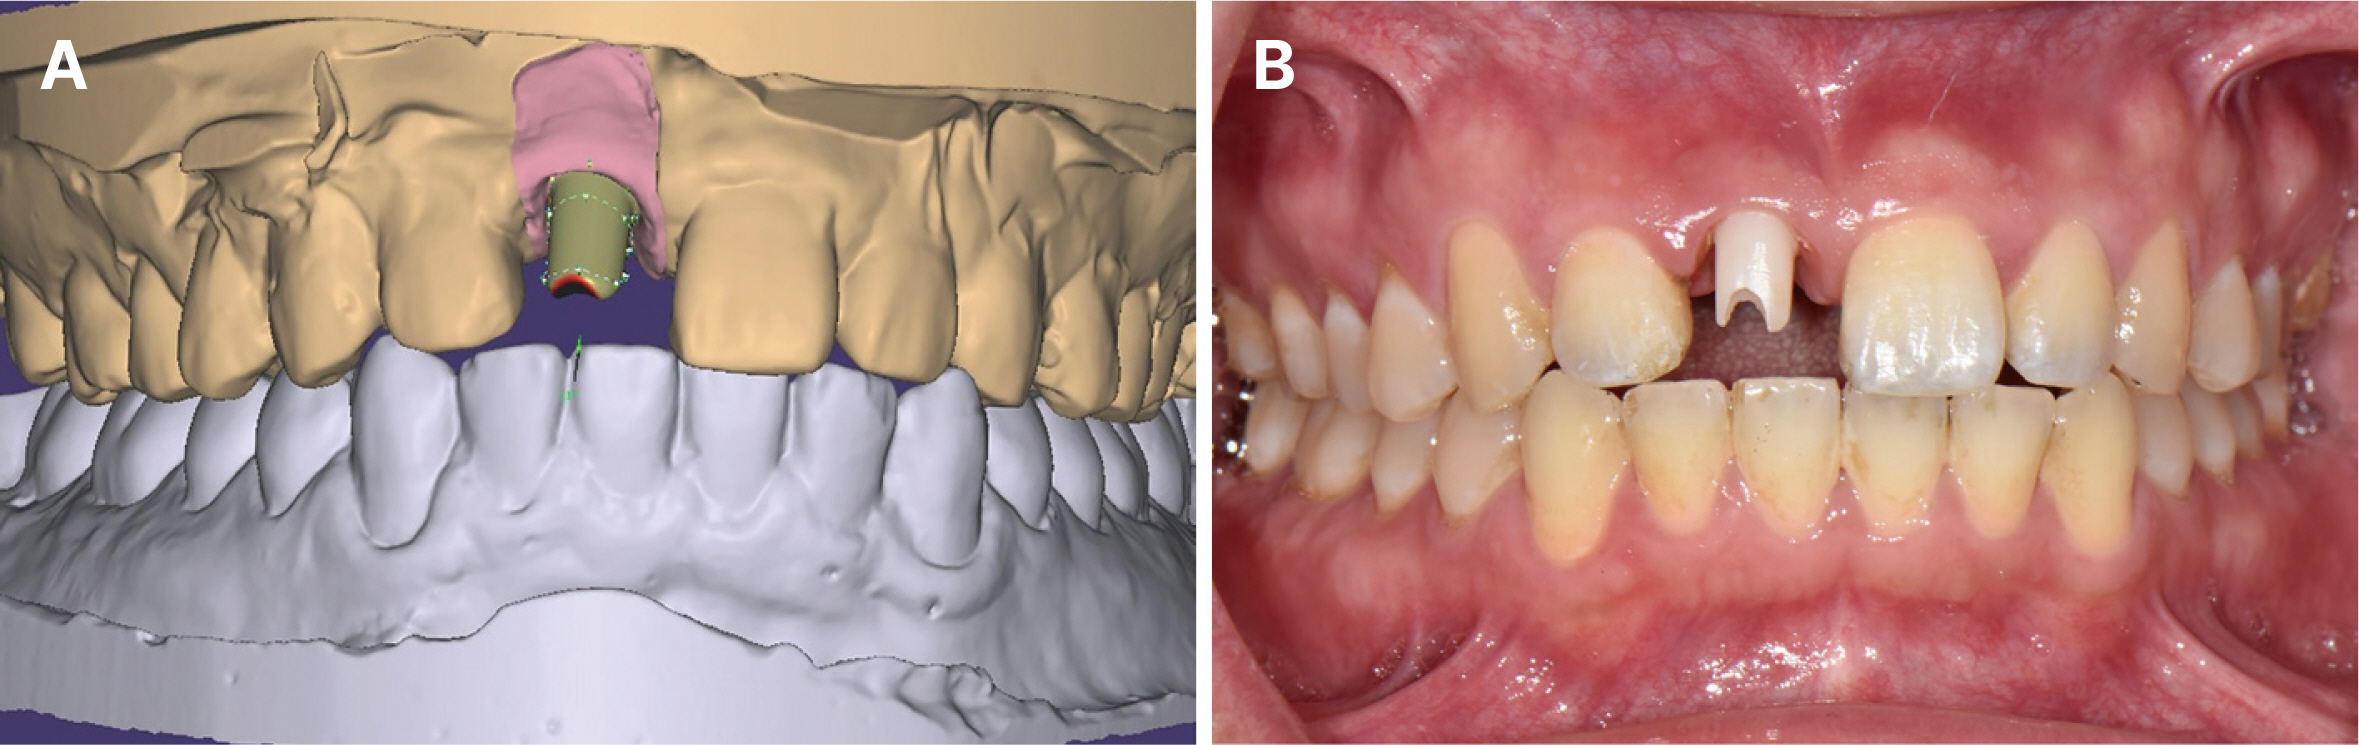

- Immediate implant placement and immediate loading in the anterior maxilla is an effective approach to rapidly address aesthetic demands. To achieve successful outcomes, bone quality, soft tissue condition, and accurate implant positioning are essential factors. For optimal results, procedures such as bone augmentation, precise implant placement, and, when necessary, soft tissue grafting should be considered. Furthermore, provisional restoration play a crucial role in achieving the desired appearance of prosthetic restorations and improving the aesthetics of the soft tissue. By performing soft tissue molding through provisional restoration, an ideal emergence profile can be established, which can be subsequently transferred to the final prosthesis, leading to a functional and aesthetically pleasing restoration. This approach aims to optimize the aesthetic outcomes in the anterior region while preserving the natural contours of the peri-implant soft tissue. In this case, a patient requiring extraction of maxillary anterior tooth underwent immediate implantation and alveolar bone grafting using a guide fabricated in advance from CT data. The patient received a provisional restoration on the same day. Subsequent steps included transitioning from the provisional prosthesis to the definitive prosthesis, ultimately achieving an aesthetically pleasing and functional implant restoration. We report this case to highlight the successful approach to maxillary anterior implant rehabilitation.